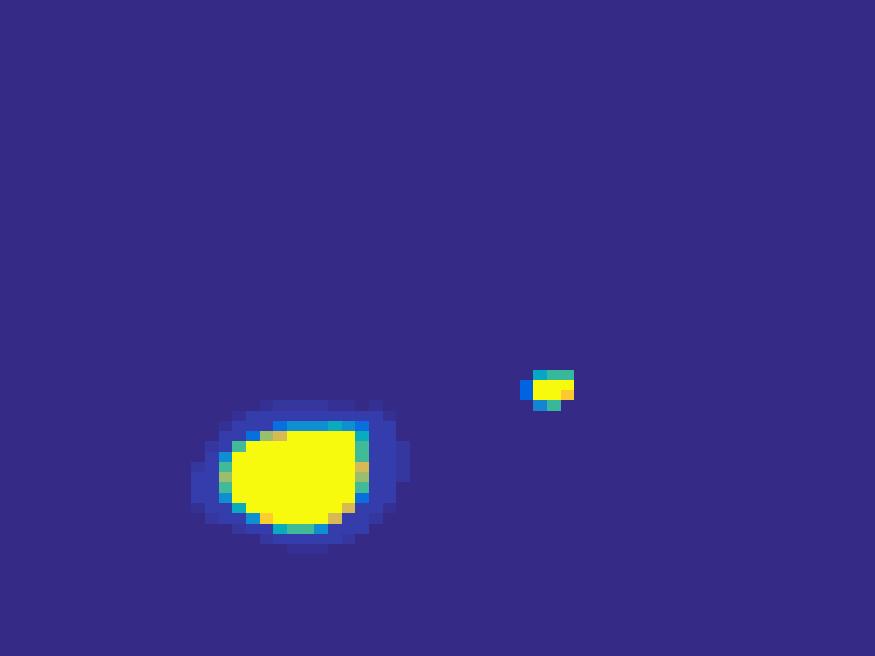

The second numerical experiment is performed on a synthetic image simulating rat’s abdomen, where the bright region represents the heart of a rat. We use the TAC in Figure 2 to simulate the dynamic images.

For the simulated images of rat’s abdomen, the same procedure is applied to generate projection data. Also, noise was added to the sinogram. Figure 5 compares the frames reconstructed by different methods. Clearly, the traditional FBP method and least square method cannot reconstruct the dynamic images with very few projections, however the proposed method reconstructs the images quite accurately. Figure 6 illustrates the comparison of the true TACs and those reconstructed by the proposed method. We can see that they are quite accurate and present small errors.